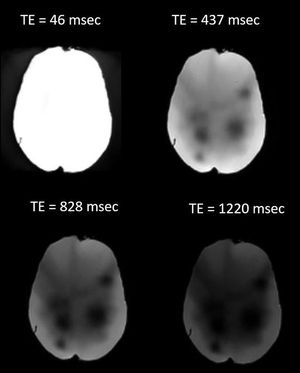

Figure illustrates the effect of different echo times (TE) on image signal-to-noise ratio (SNR)

Images were acquired using a pseudo patient head phantom. Images courtesy of Christos Tsiotsios.